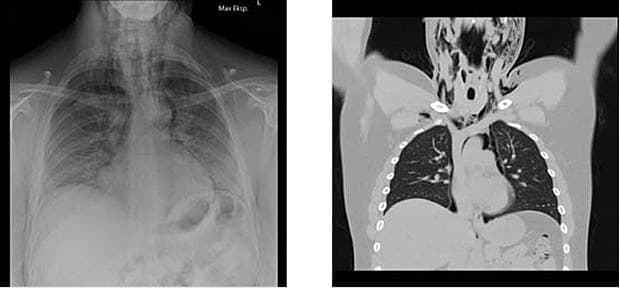

En 23-årig mand blev indlagt på mistanke om en allergisk reaktion. Han havde fået fjernet en molar i venstre underkæbe og herunder fået profylaktisk penicillin samt lokalbedøvelse. Få minutter efter proceduren tilkom der hævelse af venstre del af ansigtet, hvilket to timer senere blev kompliceret af dyspnø. Objektivt fandt man krepitation over kæbe, hals og øverste del af thorax på venstre side. En røntgenoptagelse af thorax viste luft i mediastinum. En akut CT

af thorax viste pneumomediastinum (PM). Man påbegyndte profylaktisk behandling med amoxicillin + clavulansyre og metronidazol. Efter fire dages observation på en intensivafdeling blev han udskrevet i velbefindende.